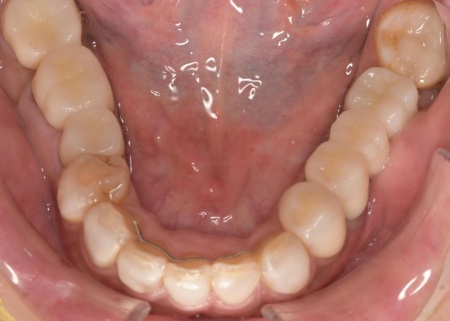

治療後

上顎の前歯2本ずつと奥歯4本(左右中切歯・第2小臼歯・第1大臼歯)、下顎の奥歯7本(左第1小臼歯・左右第2小臼歯・第1大臼歯・第2大臼歯)には、見た目が自然なセラミックの被せ物「ジルコニアクラウン」を装着しました。

加えて、上前歯4本(左右側切歯・犬歯)と下前歯5本(左右中切歯・側切歯・右下犬歯)は、ダイレクトクラウンによる修復を行いました。

ダイレクトクラウンとは、レジン(樹脂)を用いて直接歯の形を作り上げていく治療方法です。

歯を削る量が少ない、色や形を細かく調整しながら仕上げられる、治療後は必要に応じて微調整がしやすいなどのメリットがあります。